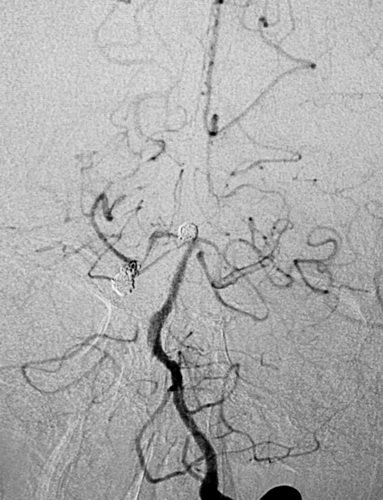

先微导管Echelon到位右侧大脑后动脉瘤,小心成篮,在保留大脑动脉通畅情况下尽可能地多栓塞动脉瘤体部与顶部,对瘤颈的栓塞不强求;分别为Presidio 3D 5mmX17cm,EV3 3D 3mmX6cm,3mmX4cm,2mmX4cm,在观察形态学弹簧圈对载瘤动脉无明显影响后实行解脱,最后造影见右侧大脑后动脉动脉瘤顶端不显影,近端于瘤颈处仍有部分显影。 之后再退至基底动脉瘤内,行部分栓塞,EV3 3D 4mmX8cm,2mmX4cm, 1.5mmX2cm,1.5mmX2cm,不用支架,是因为考虑病情较重,脑室较大,术后可能要行脑室外引流术,而支架应用则需用双抗会造成手术操作困难。后期拟再行补救支架手术。

左侧椎动脉2D造影示右侧大脑后、基底动脉顶端动脉瘤

3D成像

在处基底动脉瘤术后正侧位像